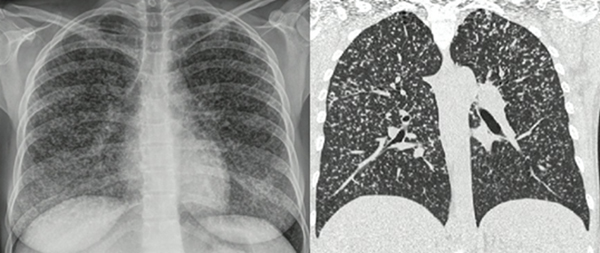

La tuberculosis pulmonar en pacientes con VIH no presenta ningún signo radiológico patognomónico. En casos de inmunosupresión leve, los hallazgos son similares a los de pacientes inmunocompetentes, con presencia de cavitaciones e infiltrados apicales; mientras que en casos de inmunosupresión severa los hallazgos habitualmente son atípicos, con predominio de afectación ganglionar y signos de diseminación hematógena, como infiltrados intersticiales difusos y patrón miliar (figura 2) (25). En esta población, el tratamiento es muy similar a personas inmunocompetentes; sin embargo, el compromiso extrapulmonar puede requerir extensión de la segunda fase de la terapia hasta doce meses (25).